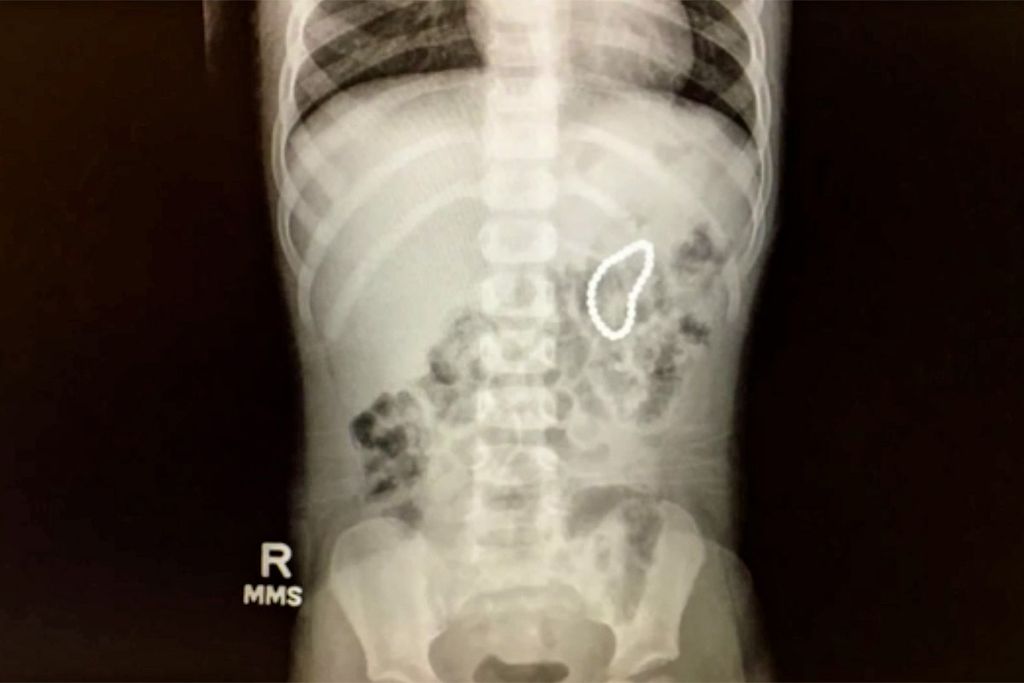

Is It Dangerous To Eat Magnets . infants and young children will put anything in their mouth. Their strength and size make them dangerous. “tiny magnets are dangerous for many reasons,” notes dr. a potentially life threatening tiktok trend, involving tiny magnets that can be easily swallowed, has triggered the. these measures are inadequate because the magnets can be swallowed by children and are 10 times stronger than common household refrigerator magnets. Learn the most commonly ingested objects, whether they’re dangerous and. “they can get stuck in the intestines and cause a blockage; Jenna wheeler, a pediatric critical care physician at orlando health arnold palmer hospital for children. magnets can find each other through tissues, and when they pinch together, it can cause perforations, twisted or blocked bowels,.

“tiny magnets are dangerous for many reasons,” notes dr. “they can get stuck in the intestines and cause a blockage; infants and young children will put anything in their mouth. Learn the most commonly ingested objects, whether they’re dangerous and. a potentially life threatening tiktok trend, involving tiny magnets that can be easily swallowed, has triggered the. Jenna wheeler, a pediatric critical care physician at orlando health arnold palmer hospital for children. magnets can find each other through tissues, and when they pinch together, it can cause perforations, twisted or blocked bowels,. Their strength and size make them dangerous. these measures are inadequate because the magnets can be swallowed by children and are 10 times stronger than common household refrigerator magnets.

Is It Dangerous To Eat Magnets magnets can find each other through tissues, and when they pinch together, it can cause perforations, twisted or blocked bowels,. Jenna wheeler, a pediatric critical care physician at orlando health arnold palmer hospital for children. Their strength and size make them dangerous. a potentially life threatening tiktok trend, involving tiny magnets that can be easily swallowed, has triggered the. these measures are inadequate because the magnets can be swallowed by children and are 10 times stronger than common household refrigerator magnets. infants and young children will put anything in their mouth. “they can get stuck in the intestines and cause a blockage; “tiny magnets are dangerous for many reasons,” notes dr. Learn the most commonly ingested objects, whether they’re dangerous and. magnets can find each other through tissues, and when they pinch together, it can cause perforations, twisted or blocked bowels,.